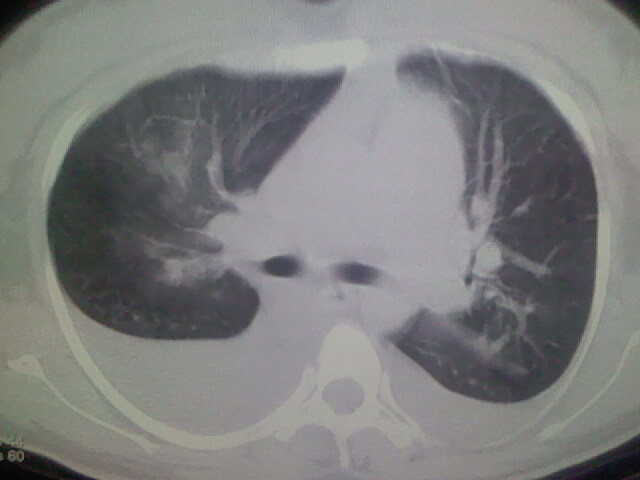

女,24,剖腹产后,突觉胸痛,干咳,不能平卧

产后心衰

临床资料及影象表现支持围产期扩张型心肌病改变,心衰。

肺水肿,双侧胸腔积液,心影增大.考虑妊娠心脏病

产后心衰、肺水肿

考虑产后心肌病,心功能不全,肺水肿,双侧胸腔积液。

风心、心衰。两肺水肿、感染灶及胸水是心衰表现